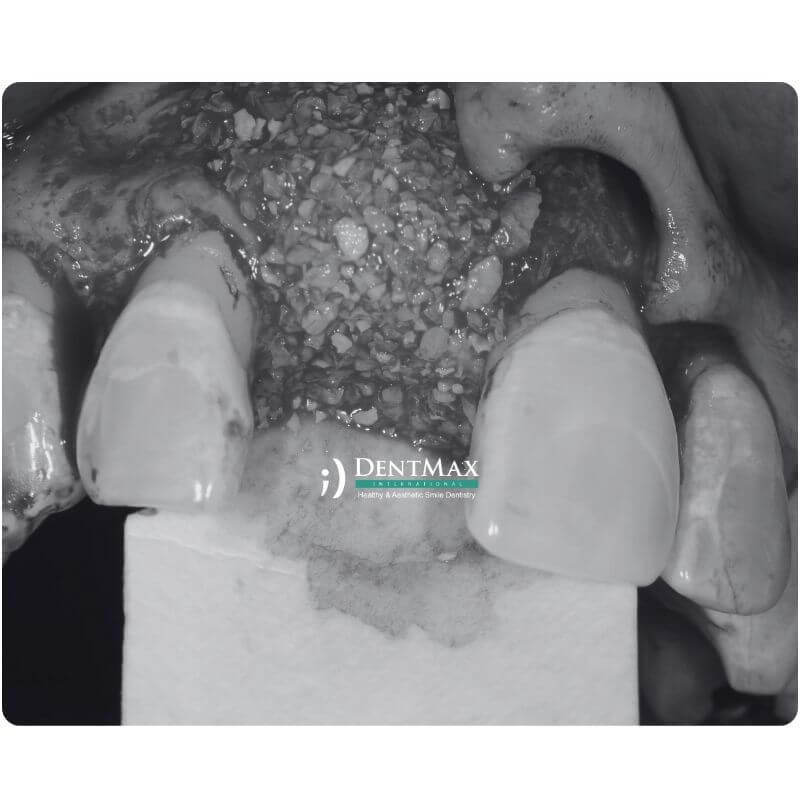

العنوان: كم من الوقت يجب أن تنتظر لزراعة الأسنان بعد زراعة العظام؟